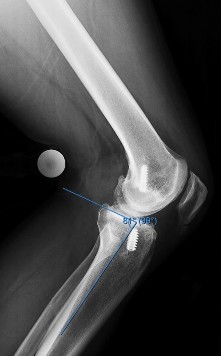

A 40-year-old skier sustains a highly comminuted Schatzker Type VI tibial plateau fracture.

Over the next few hours, he develops tense swelling of the lower leg, paresthesias in the first web space, and pain out of proportion to the injury with passive toe extension. If compartment pressures are measured to confirm acute compartment syndrome, which of the following provides the most reliable threshold for diagnosing the condition?

Explanation

Acute compartment syndrome is primarily a clinical diagnosis, but pressure measurements are critical in equivocal cases or obtunded patients. The most reliable and widely accepted metric is the delta pressure (ΔP), calculated as the Diastolic Blood Pressure minus the Intracompartmental Pressure. A delta pressure of less than 30 mmHg strongly supports the diagnosis and dictates emergent fasciotomy, as capillary perfusion relies on the gradient with diastolic pressure.